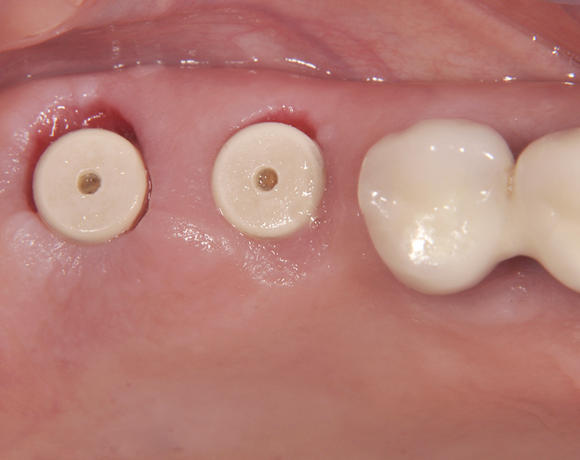

Beim Internen Sinuslift wird durch die Implantatbohrung ohne die Schleimhaut des Kieferhöhlenbodens zu durchbrechen Knochenmaterial unter die Schleimhaut geschoben, um neues Knochenwachstum, um das in die Kieferhöhle eingeschraubte Implantat, zu bekommen.

Der vorliegende Patientenfall zeigt eine komplette Neuversorgung der vorhandenen Metallkeramikkronen mit vollkeramischen Restaurationen. Zusätzlich wurde im Oberkiefer die Zahnreihe mit zwei Implantaten, für die fehlenden Molaren, ergänzt. Da keine ausreichende Knochenhöhe vorhanden war wurde ein interner Sinuslift geplant.